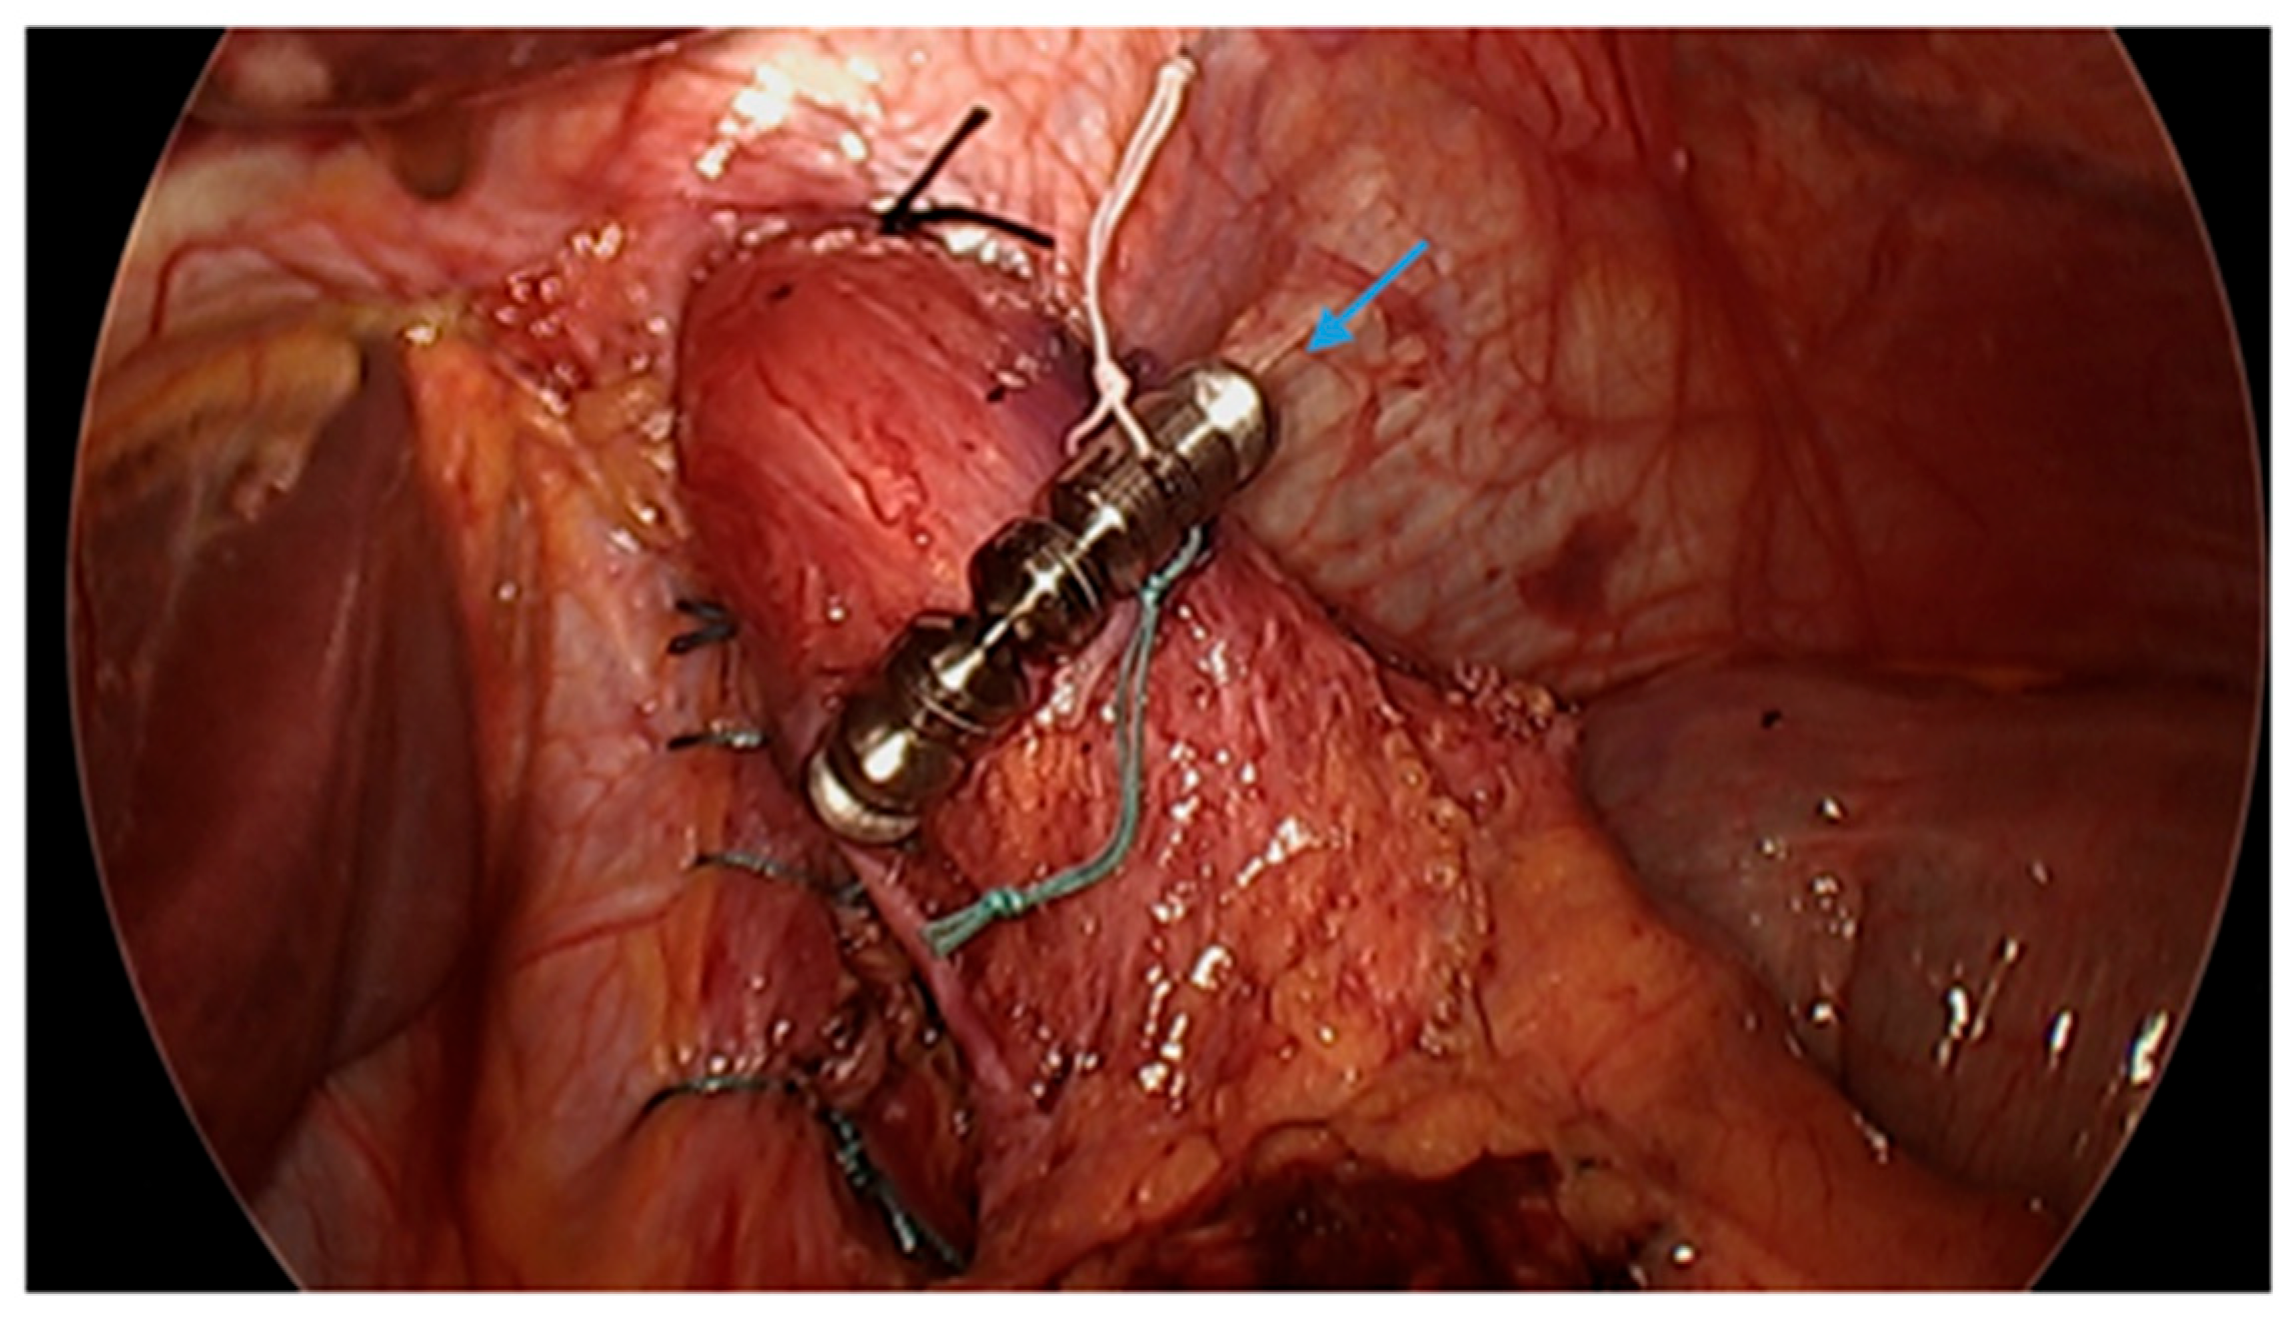

Figure 9.

Laparoscopic image reveals a patient post-sleeve gastrectomy with a defect in the diaphragmatic hiatus (arrow) and subsequent gastroesophageal reflux disease. Image courtesy of Dr. Brian Louie, Chief of Thoracic Surgery at Swedish Medical Center in Seattle, Washington, USA.

Figure 10.

Laparoscopic image demonstrates hiatal hernia repair and successful placement of a magnetic sphincter augmentation device (arrow) around the esophagus in a patient post-sleeve gastrectomy with gastroesophageal reflux disease. Image courtesy of Dr. Brian Louie, Chief of Thoracic Surgery at Swedish Medical Center in Seattle, Washington, USA.